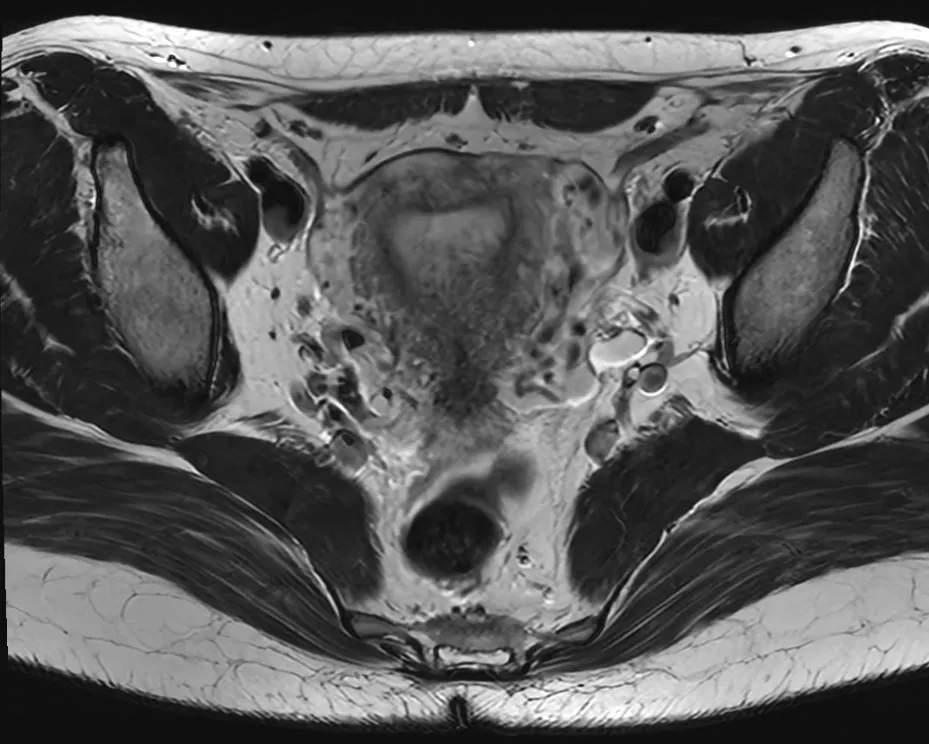

Eksempler på MR Scanninger

En gynækologisk MR-scanning af kvindelige kønsorganer er en skånsom og præcis undersøgelse, der giver detaljerede billeder af underlivet. Vores 3 tesla MR-scanner bruger et magnetfelt og radiobølger til at skabe tydelige billeder af bløddele som livmoder, æggestokke og omkringliggende væv – helt uden brug af røntgenstråling.

Denne type undersøgelse er særligt god til at undersøge og diagnosticere forskellige tilstande i underlivet, der kan være svære at opdage med andre metoder. MR-scanning kan give et klart og detaljeret billede af eventuelle forandringer eller sygdomme i de kvindelige kønsorganer.